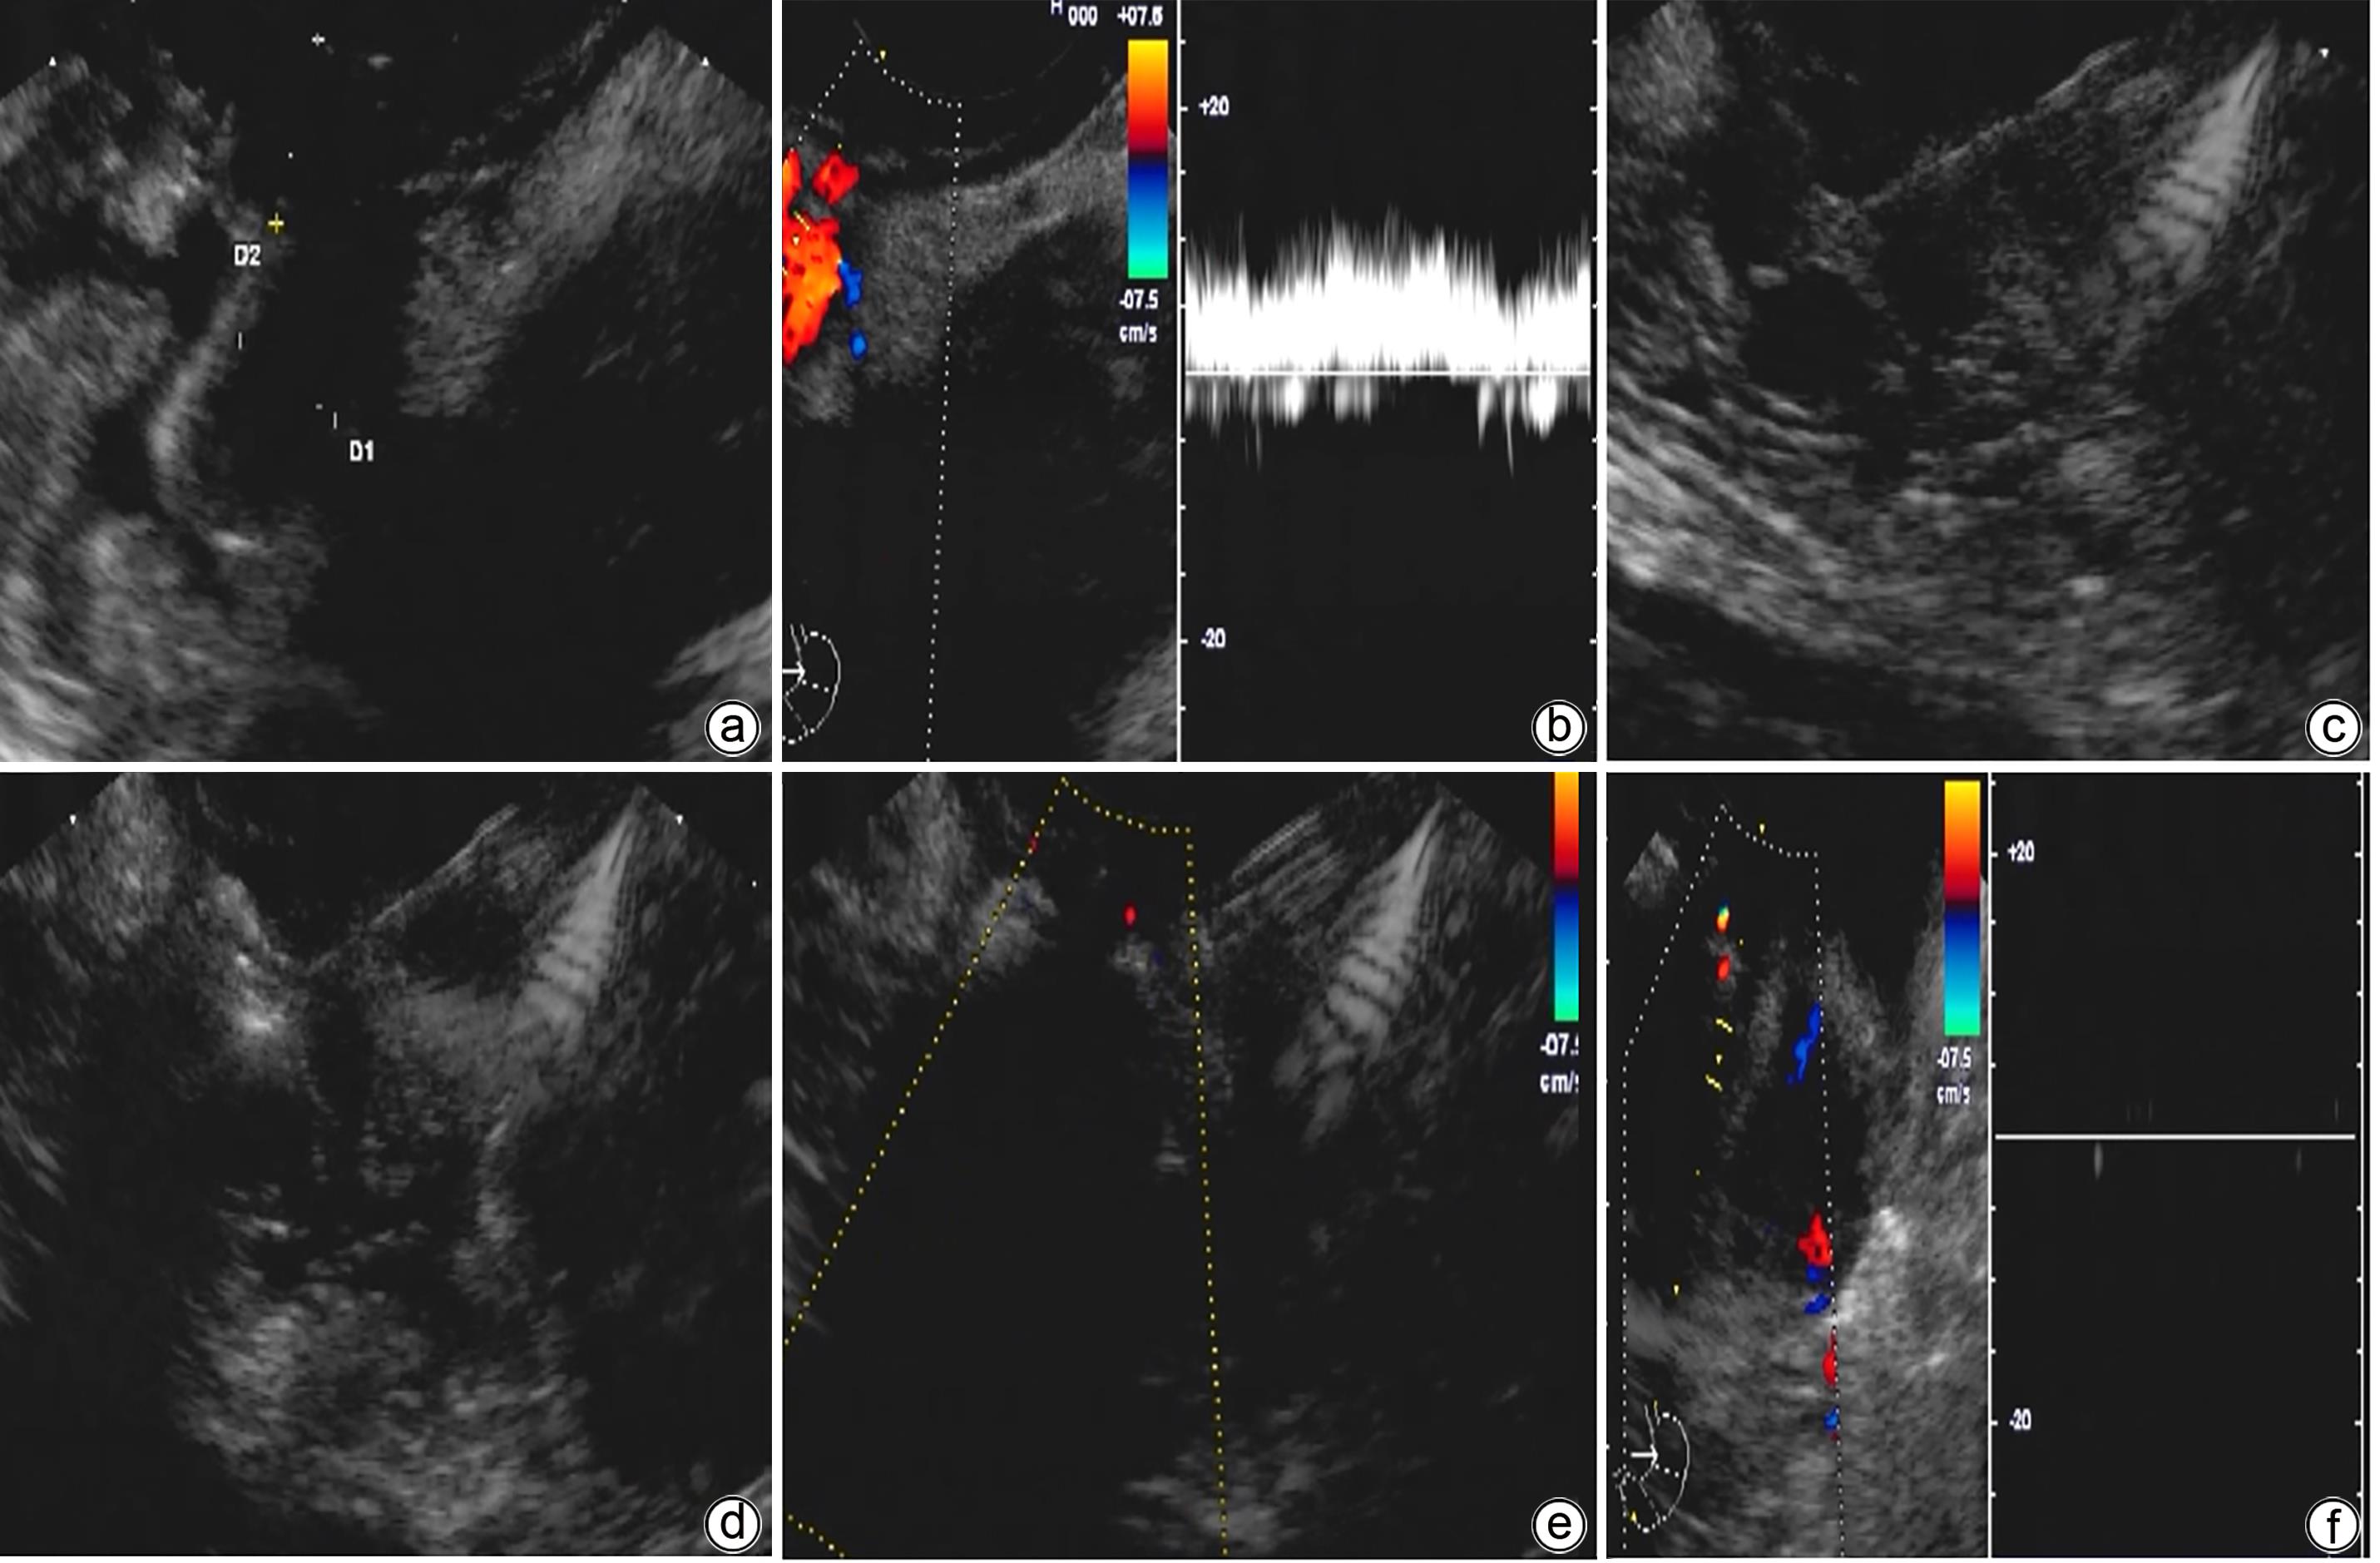

The preliminary therapeutic effect of endoscopic ultrasound-guided tissue adhesive injection with the assistance of metal clips in treatment of cirrhotic patients with gastric varices and gastric-renal shunt

Jiali MA, Zhenglin AI, Julong HU, Yu JIANG, Yuling ZHOU, Xiuxia LIANG, Hongshan WEI, Ping LI

2024, 40(4): 734-738. DOI: 10.12449/JCH240415

Abstract(1116) HTML (309) PDF (1036KB)(61)

Abstract:

Objective  To investigate the safety and efficacy of endoscopic ultrasound-guided tissue adhesive injection with the assistance of metal clips in the treatment of cirrhotic patients with gastric varices and gastric-renal shunt (GRS).  Methods  The patients who attended Beijing Ditan Hospital, Capital Medical University, due to liver cirrhosis and gastric varices from February to June 2023 were enrolled, and all patients were confirmed to have GRS and received endoscopic ultrasound-guided tissue adhesive injection with the assistance of metal clips. The primary evaluation index was alleviation or disappearance of varicose veins after surgery, and the secondary evaluation indices were surgical completion and complications.  Results  A total of 11 patients were enrolled in this study, among whom there were 7 male patients and 4 female patients, with a median age of 55 years. Of all patients, 1 had Child class A liver function, 7 had Child class B liver function, and 3 had Child class C liver function. The maximum (median) diameter of the shunt was 8 mm, and the minimum (median) diameter of the shunt was 4 mm. The median blood flow velocity of the target vessel was 11 cm/s before treatment and 5 cm/s after occlusion with metal clips. The median amount of tissue adhesive injected was 2 mL, and the amount of lauromacrogol used was 1 mL. Disappearance of blood flow signals was observed in all patients after surgery (100%), and the success rate of surgery was 100%. No patient experienced rebleeding after follow-up for 6 weeks. Gastroscopy at 1 month after surgery showed that gastric varices were eradicated or almost disappeared in 9 patients and were alleviated in 2 patients.  Conclusion  Endoscopic ultrasound-guided tissue adhesive injection with the assistance of metal clips is a feasible, safe, and effective treatment method for cirrhotic patients with gastric varices and GRS.